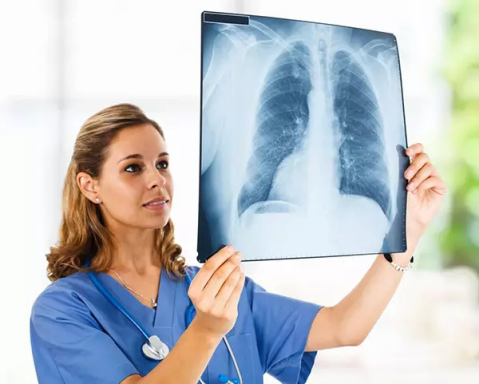

X光攝影(平片)

X光會(huì)穿透人體,由于人體各部位組織密度厚度不同,吸收的X光機(jī)的劑量不同,到達(dá)底片的X光的量不同,底片就會(huì)顯現(xiàn)出黑白不同的顏色。

優(yōu)點(diǎn):快捷、價(jià)廉、影像清晰度高

缺點(diǎn):平片檢查,無(wú)法進(jìn)行三維檢查

3、胸部——粗看X光平片,細(xì)看CT

X光胸片可粗略檢查肺、心影、主動(dòng)脈弓、肋骨等,可以檢查有無(wú)肺紋理增多、肺內(nèi)較大腫塊、主動(dòng)脈結(jié)鈣化等。胸部CT檢查顯示出的結(jié)構(gòu)更清晰,對(duì)胸部病變檢出敏感性和準(zhǔn)確性均優(yōu)于常規(guī)X光胸片,特別是對(duì)于篩查早期肺癌有重大意義。而磁共振成像對(duì)于肺內(nèi)疾病的診斷,應(yīng)用非常有限。